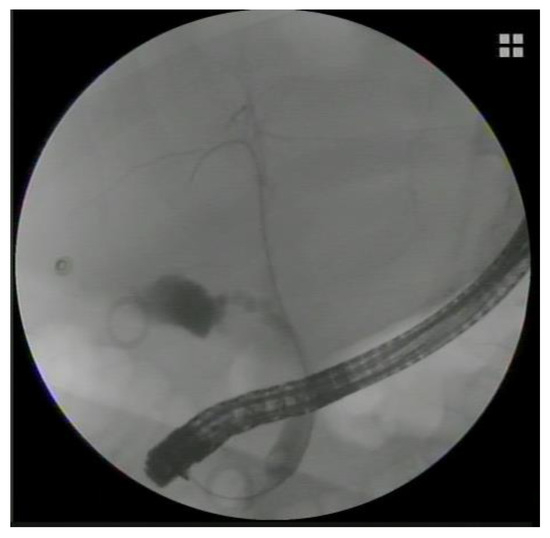

2. Transpapillary Endoscopic Gallbladder Drainage: Technical Aspects

- AbiMansour, J.P.; Law, R.J.; Storm, A.C.; Chandrasekhara, V. Tips and tricks for endoscopic transpapillary gallbladder drainage. VideoGIE 2023, 8, 474–477. [Google Scholar] [CrossRef] [PubMed]

- Ridtitid, W.; Piyachaturawat, P.; Teeratorn, N.; Angsuwatcharakon, P.; Kongkam, P.; Rerknimitr, R. Single-operator peroral cholangioscopy cystic duct cannulation for transpapillary gallbladder stent placement in patients with acute cholecystitis at moderate to high surgical risk (with videos). Gastrointest. Endosc. 2020, 92, 634–644. [Google Scholar] [CrossRef]

- Barkay, O.; Bucksot, L.; Sherman, S. Endoscopic transpapillary gallbladder drainage with the SpyGlass cholangiopancreatoscopy system. Gastrointest. Endosc. 2009, 70, 1039–1040. [Google Scholar] [CrossRef]

- Shin, J.U.; Lee, J.K.; Kim, K.M.; Lee, K.H.; Lee, K.T. Endoscopic naso-gallbladder drainage by using cholangioscopy for acute cholecystitis combined with cholangitis or choledocholithiasis (with video). Gastrointest. Endosc. 2012, 76, 1052–1055. [Google Scholar] [CrossRef]